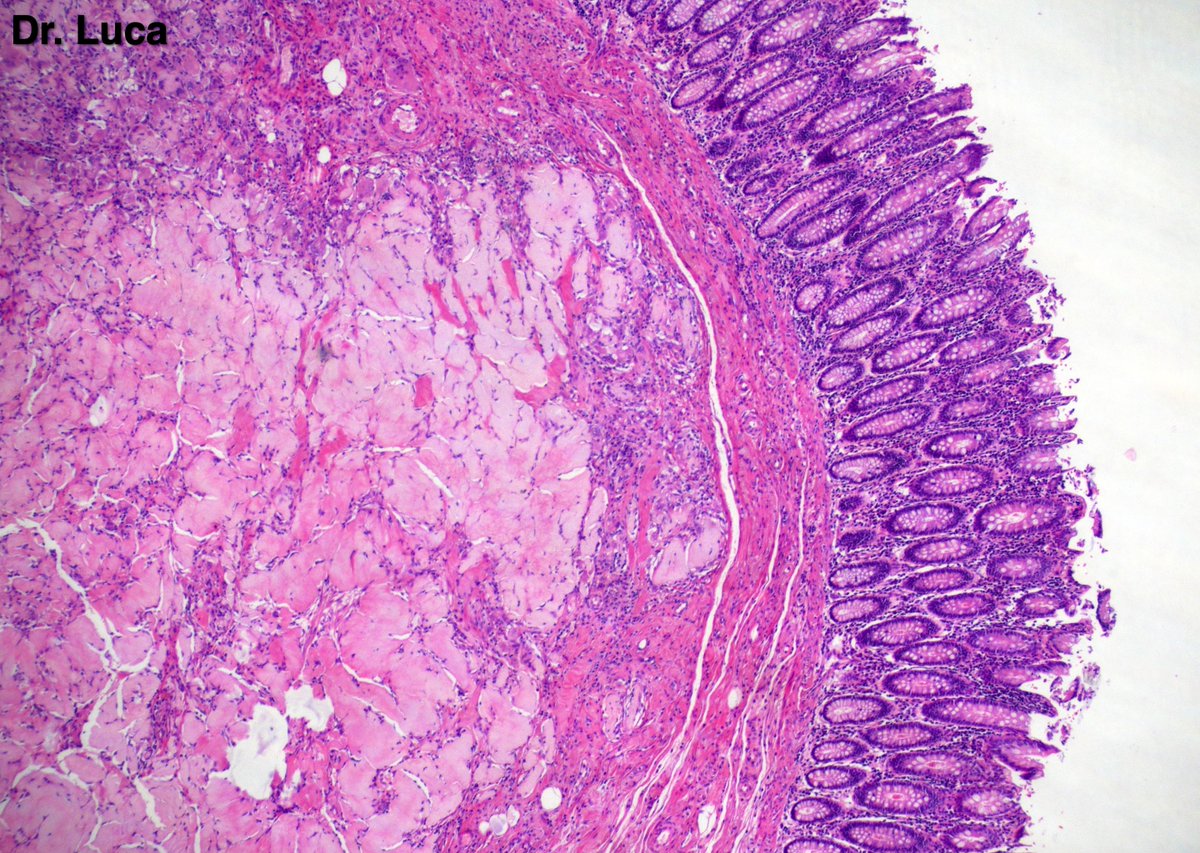

@Pathmath1 @SumantaDas_7 @PoloniaAntonio @ivanaspath @AnapathResident @bansar7 @goziemnweke @Teclis82 @Dr_Brian_Cox @DrBMcGinn @ariella8 @nusrat_xahra @DrRusella_Mirza @glinglerimek @kis_lorand @Venkateshgilly2 @DrBonita16 @DrPayelMondal @DrGeeONE @anjuthevirgo @niki_2389 @pepeheffernan @AngeloCassisa @NeoCrazee @TristanRutland7 Yes, it's a cancer with PNI...I show you the "superficial" layer of this cancer...what is the cancer? and what is the organ? #Pathology #GIpath #PathTwitter #PathResidents #pathboards